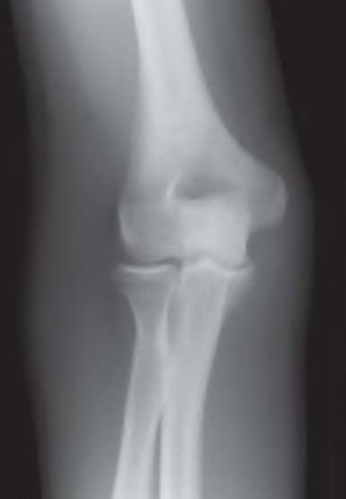

A 35-year-old woman reports wrist pain after a fall onto an outstretched hand. On exam, she has focal tenderness over the wrist snuffbox. A radiograph and CT image are shown in Figures A and B. What is the proper treatment of her injury?